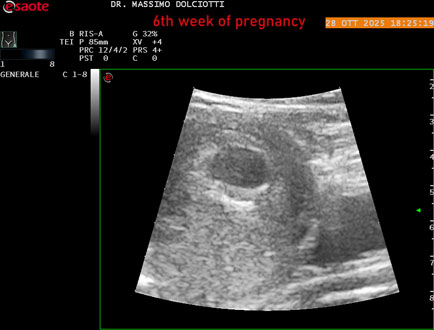

Data inserimento: 29/10/2025

Ecografia del: 28/10/2025

Strumento: Esaote MyLab Eight

Sonda: Convex Multifrequenza 1-8 MHz

Età Paziente: F 35 anni

Motivazione dell'esame: amenorrea.

Commento all'esame: le immagini ed il video documentano in utero il sacco gestazionale, il sacco vitellino e presenza di embrione delle dimensioni di 4,7 mm (CRL), con iniziale attività cardiaca, documentata nel video.

Conclusioni: gravidanza alla 6° settimana di gestazione (pregnancy to the 6th week of gestation).